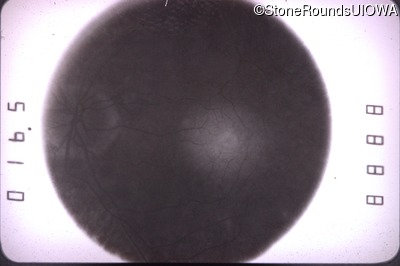

Goldmann Visual Field - Left - 20/60 +2

Exemplar